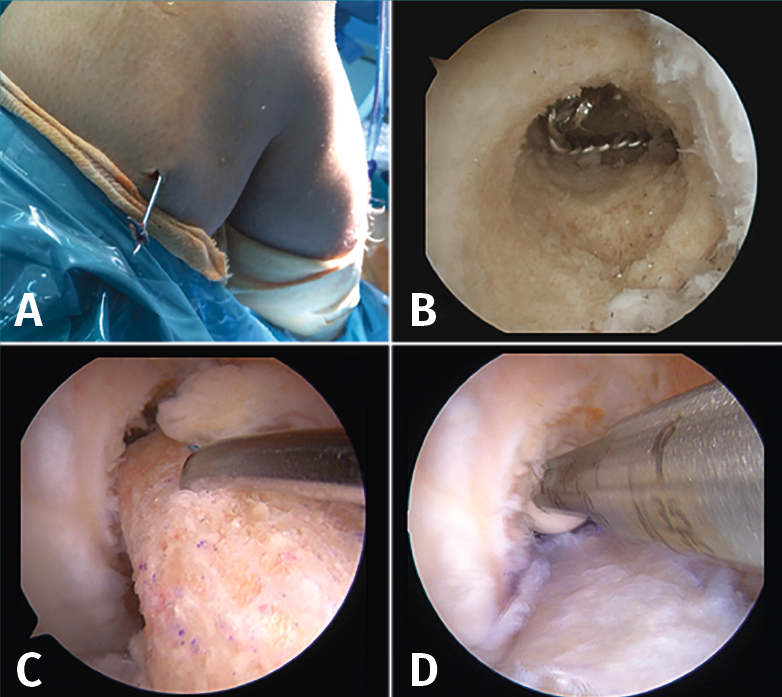

La cirugía de recambio de la plastia en un tiempo se inicia habitualmente con una revisión artroscópica convencional a través de los portales anteromedial y anterolateral. Después de la revisión artroscópica, se realiza la limpieza de los restos de la plastia previa, se retira el material de fijación y, posteriormente, se reconstruye el LCA con la nueva plastia (Figura 6).

Figura 6. Cirugía de revisión del ligamento cruzado anterior (LCA) en un tiempo. A: retirada del material de fijación previo. Casualmente, al utilizar el mismo túnel femoral la aguja guía permitió localizar y extraer el implante de fijación extracortical; B: restos de material en el túnel femoral que deben retirarse previamente a la introducción de la nueva plastia; C-D: el sobredimensionamiento del túnel femoral previo puede compensarse con un taco óseo de mayor diámetro asociado a un tornillo interferencial.

En cuanto al túnel óseo femoral, cuando está localizado en la posición correcta, se suele realizar el nuevo túnel óseo con un diámetro mínimamente superior al previo con el objetivo de retirar los restos de la plastia. La longitud del nuevo túnel dependerá de la plastia que el cirujano haya escogido para la cirugía. En el caso de un injerto con taco óseo, este se ajustará al diámetro del túnel realizado y, posteriormente, se fijará con un tornillo interferencial o bien un sistema de fijación cortical externa en el fémur. Cuando el túnel femoral se encuentre lejos de la localización del nuevo túnel, se puede rellenar el túnel previo con injerto óseo o un tornillo interferencial, con el fin de evitar la fractura de la pared del nuevo túnel. Esto puede suceder cuando se realiza una revisión sobre una técnica de reconstrucción transtibial previa (Figura 7).

Figura 7. Cirugía de revisión en un tiempo en los casos de técnica transtibial previa. A: la guía utilizada habitualmente para la técnica transtibial dirigía el túnel femoral lejos de la huella anatómica femoral del ligamento cruzado anterior (LCA); B: relleno del túnel previo con un nuevo tornillo interferencial; C-D: cuando el túnel femoral previo queda muy alejado de la localización anatómica y no compromete la nueva reconstrucción, no es imprescindible rellenarlo de injerto óseo.

En el caso del túnel tibial, cuando se realiza un recambio en un tiempo suele ser porque el túnel esta correctamente posicionado. Después de realizar el abordaje anterointerno en la tibia proximal, se localiza el punto de entrada del túnel previo en la cortical de la tibia. Con la misma guía con la que realizamos habitualmente el túnel tibial en un LCA primario, se realiza de nuevo el túnel tibial limpiando los restos de la plastia y del sistema de fijación previos. Posteriormente, dependiendo del diámetro final del túnel y del tipo de plastia que se va a utilizar, se realizará la fijación tibial con un nuevo tornillo interferencial, asociándolo en ocasiones a una fijación adicional cortical en la tibia.